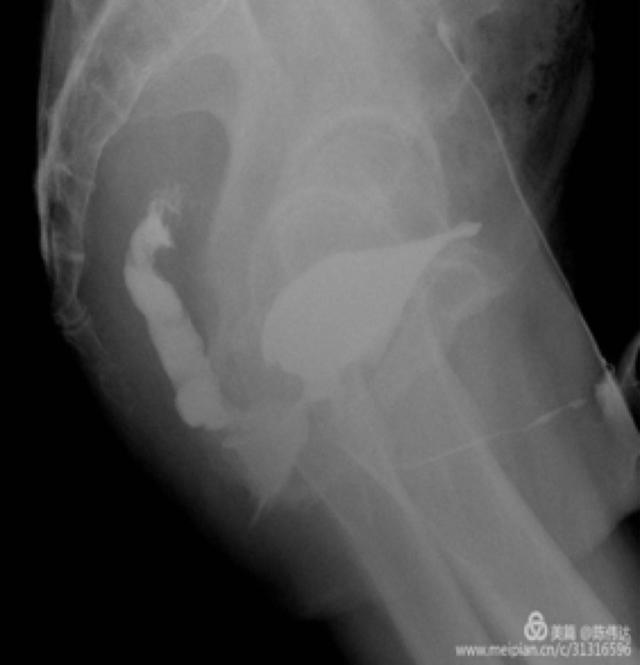

膀胱造影图(我亲自管的病人)

膀胱镜、直肠镜、尿道逆行造影、膀胱造影、CT、核磁等。一般诊断不难,难在治疗!